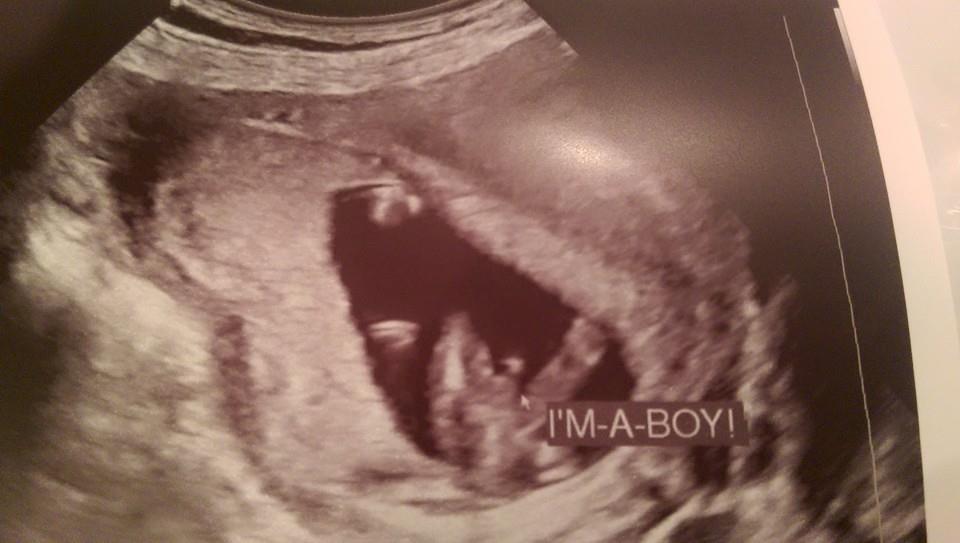

Hello! New here! Two boys already, and pregnant with our third. We went for an elective scan on Saturday, I was thirteen weeks plus two days. Tech was very confident with saying boy, but I know its still a bit early. Any chance of hearing girl later on?Attachment 24951Attachment 24951Attachment 24952